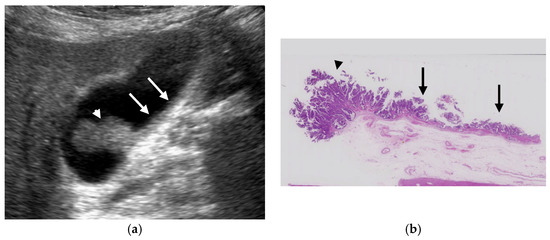

Recently, several GBCs concomitant with fundal type ADM have been reported [7,35,37,38,39,40,41] (Figure 8). These GBCs showed well-circumscribed papillary growth just above the surface mucosa of ADM or inside RAS. Therefore, even in cases with the presence of RAS, the mucosal surface of ADM and inside RAS should be evaluated in detail to detect concomitant GBCs. Tang et al. [35] reported that the discontinuity of the wall on CEUS was helpful for the diagnosis of ADM with GBC.

Figure 8. GBC concomitant with localized ADM. (a) US showed a papillary GPL (arrow) with dilated cystic lesions in the fundus. (b) Histopathologically, a papillary GBC (arrow) arose in the surface mucosa of localized ADM and cystic lesions were corresponding to dilated RASs (*: dilated RAS). Reprinted with permission from ref. [7]. Copyright 2021 Japan Society of Ultrasonics in Medicine.